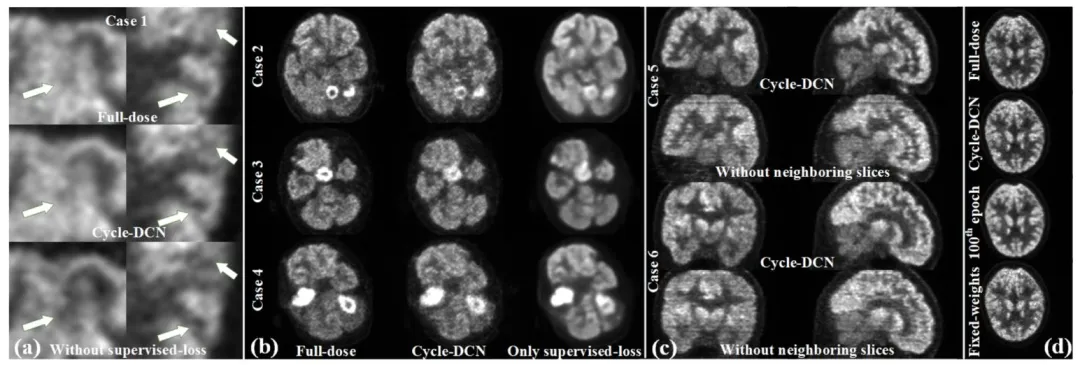

The proposed Cycle-DCN model was systematically compared with several established image denoising and restoration methods, including widely used U-Net, classic denoising model DnCNN (Zhang et al., 2017), the more recent image restoration model CGNet (Ghasemabadi et al., 2024), the Swin Transformer-based SwinIR, CycleGAN, and three diffusion-based approaches: DDPM-PET, PET-CM, and BC-DPM. Table 1provides the quantitative results, showing the mean, standard deviation, and statistical significance based on paired t-tests for each evaluation metric. Fig. 4(a) presents a visual comparison of a representative slice across the nine models, along with the corresponding full-dose and low-dose images at three different dose levels.For ¼ low-dose images, the PSNR, SSIM, and NRMSE metrics are comparable across all evaluated models. While DnCNN and SwinIR slightly outperforms Cycle-DCN in some measures, these differences are not statistically significant (p > 0.05). In contrast, for the more challenging 1/24 low-dose images, Cycle-DCN achieves superior metric values. The three diffusion-based methods—DDPM-PET, PET-CM, and BC-DPM—consistently yielded inferior performance under all the three low-dose conditions. As shown in Fig. 4(a), U-Net and DnCNN result in excessive smoothing, leading to increased deviation from the full-dose images at lower dose levels, with small sulci becoming nearly indistinguishable. However, Cycle-DCN remains closer to the full-dose images, demonstrating better robustness. In the enlarged views in Fig. 4(b), Cycle-DCN uniquely preserves brain structures such as sulci and gyri, producing visual outputs more consistent with full-dose images compared to other models. Among the three diffusion-based methods, DDPM-PET produced visually promising results across all dose levels. However, the performance of BC-DPM (trained unconditionally) and PET-CM (with two-step sampling) deteriorated rapidly as the dose decreased, resulting in significantly degraded image quality.

4.1 定量评估 4.1.1 峰值信噪比(PSNR)、结构相似性指数(SSIM)及归一化均方根误差(NRMSE)对比 将所提Cycle-DCN模型与多种已有的图像去噪和恢复方法进行了系统对比,包括广泛使用的U-Net、经典去噪模型DnCNN(Zhang等,2017)、较新的图像恢复模型CGNet(Ghasemabadi等,2024)、基于Swin Transformer的SwinIR、CycleGAN,以及三种基于扩散的方法(DDPM-PET、PET-CM和BC-DPM)。表1给出了定量结果,包括各评估指标的均值、标准差以及基于配对t检验的统计显著性。图4(a)展示了九种模型在三个不同剂量水平下,代表性切片的视觉对比,同时呈现了对应的全剂量和低剂量图像。 对于¼低剂量图像,所有评估模型的PSNR、SSIM和NRMSE指标表现相当。尽管DnCNN和SwinIR在部分指标上略优于Cycle-DCN,但这些差异无统计学意义(p > 0.05)。相比之下,在更具挑战性的1/24低剂量图像中,Cycle-DCN取得了更优的指标值。三种基于扩散的方法(DDPM-PET、PET-CM和BC-DPM)在所有三个低剂量条件下均表现出持续劣势。如图4(a)所示,U-Net和DnCNN存在过度平滑问题,导致在低剂量水平下与全剂量图像的偏差增大,细小脑沟几乎无法区分。而Cycle-DCN始终更接近全剂量图像,展现出更强的鲁棒性。在图4(b)的放大视图中,Cycle-DCN独特地保留了脑沟、脑回等脑部结构,生成的视觉结果比其他模型更接近全剂量图像。在三种基于扩散的方法中,DDPM-PET在所有剂量水平下均产生了视觉上较理想的结果,但无监督训练的BC-DPM和两步采样的PET-CM的性能随剂量降低迅速下降,导致图像质量显著退化。

Fig. 13. (a) Comparison of the enlarged full-dose images, denoised images using Cycle-DCN, and denoised images from the model without supervised loss; (b) Comparison of the full-dose image, denoised images from Cycle-DCN, and denoised image from the model using only supervised loss for 3 different cases; © Comparison of denoised images in coronal (left column), and sagittal planes (right column) for two representative cases with/without neighboring slices assisted; (d) Denoised images under different loss weighting strategies.

图13 (a) 全剂量图像放大图、Cycle-DCN去噪图像与无监督损失模型去噪图像的对比;(b) 3个不同病例的全剂量图像、Cycle-DCN去噪图像与仅使用监督损失模型去噪图像的对比;© 两个代表性病例在有无相邻切片辅助情况下,冠状位(左列)和矢状位(右列)去噪图像的对比;(d) 不同损失权重策略下的去噪图像。